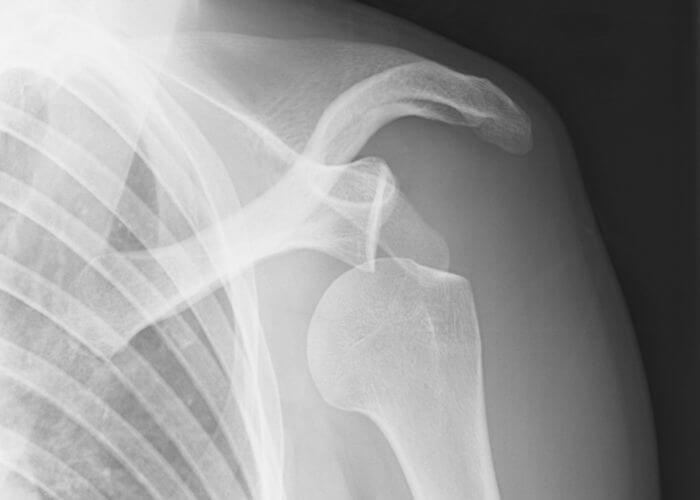

What Is An Unstable Shoulder . The term “shoulder instability” is used to describe what happens when the humeral head separates from the glenoid. Shoulder instability is defined as. There are three common ways that a shoulder can become unstable: This can be a very quick partial. Shoulder instability is an issue affecting the structures surrounding the shoulder joint, typically when these structures do not work. Chronically unstable shoulders can lead to loose shoulder joints that slip out of. Do your shoulders feel like they are loose? The glenohumeral joint of the shoulder has the highest range of motion of the human body and the most inherently unstable, often developing recurrent instability. Learn all about shoulder instability, common signs and symptoms, and the ultimate guide of how to prevent shoulder instability! Shoulder instability occurs when the arm’s ball joint moves in and out of the shoulder socket joint. When the head of the humerus. Severe injury, or trauma, is often the cause of an initial shoulder dislocation. Shoulder instability happens when the ball of the shoulder isn't restrained properly by ligaments or cartilage and slides out of the shoulder socket,.